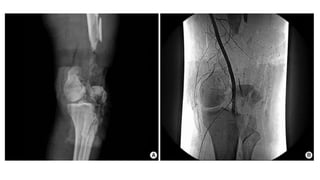

Investigations

X-ray :

- obtain standard AP

and Lateral view

CT :

• obtain with frontal and

sagittal reconstructions

Hoffa fracture

Angiography :

• Indicated when diminished distal pulses after gross alignment

restored

• Consider if associated with knee dislocation

Investigations X-ray : - obtainstandard AP and Lateral view

CT : • obtainwith frontal and sagittal reconstructions

Angiography : • Indicatedwhen diminished distal pulses after gross alignment restored • Consider if associated with knee dislocation